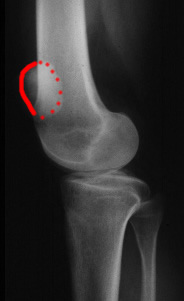

La bascule de la rotule vers l'extérieur.

Elle est visible sur des radios ou un scanner. Elle est la résultante de la faiblesse ou de la rupture de l'aileron interne et de la possible rétraction de l'aileron externe.

La rotation de la rotule

Lorsque l'aileron interne est distendu ou rompu, la radio de profil du genou en extension, quadriceps contracté, montre la rotule presque de face, preuve de sa rotation.